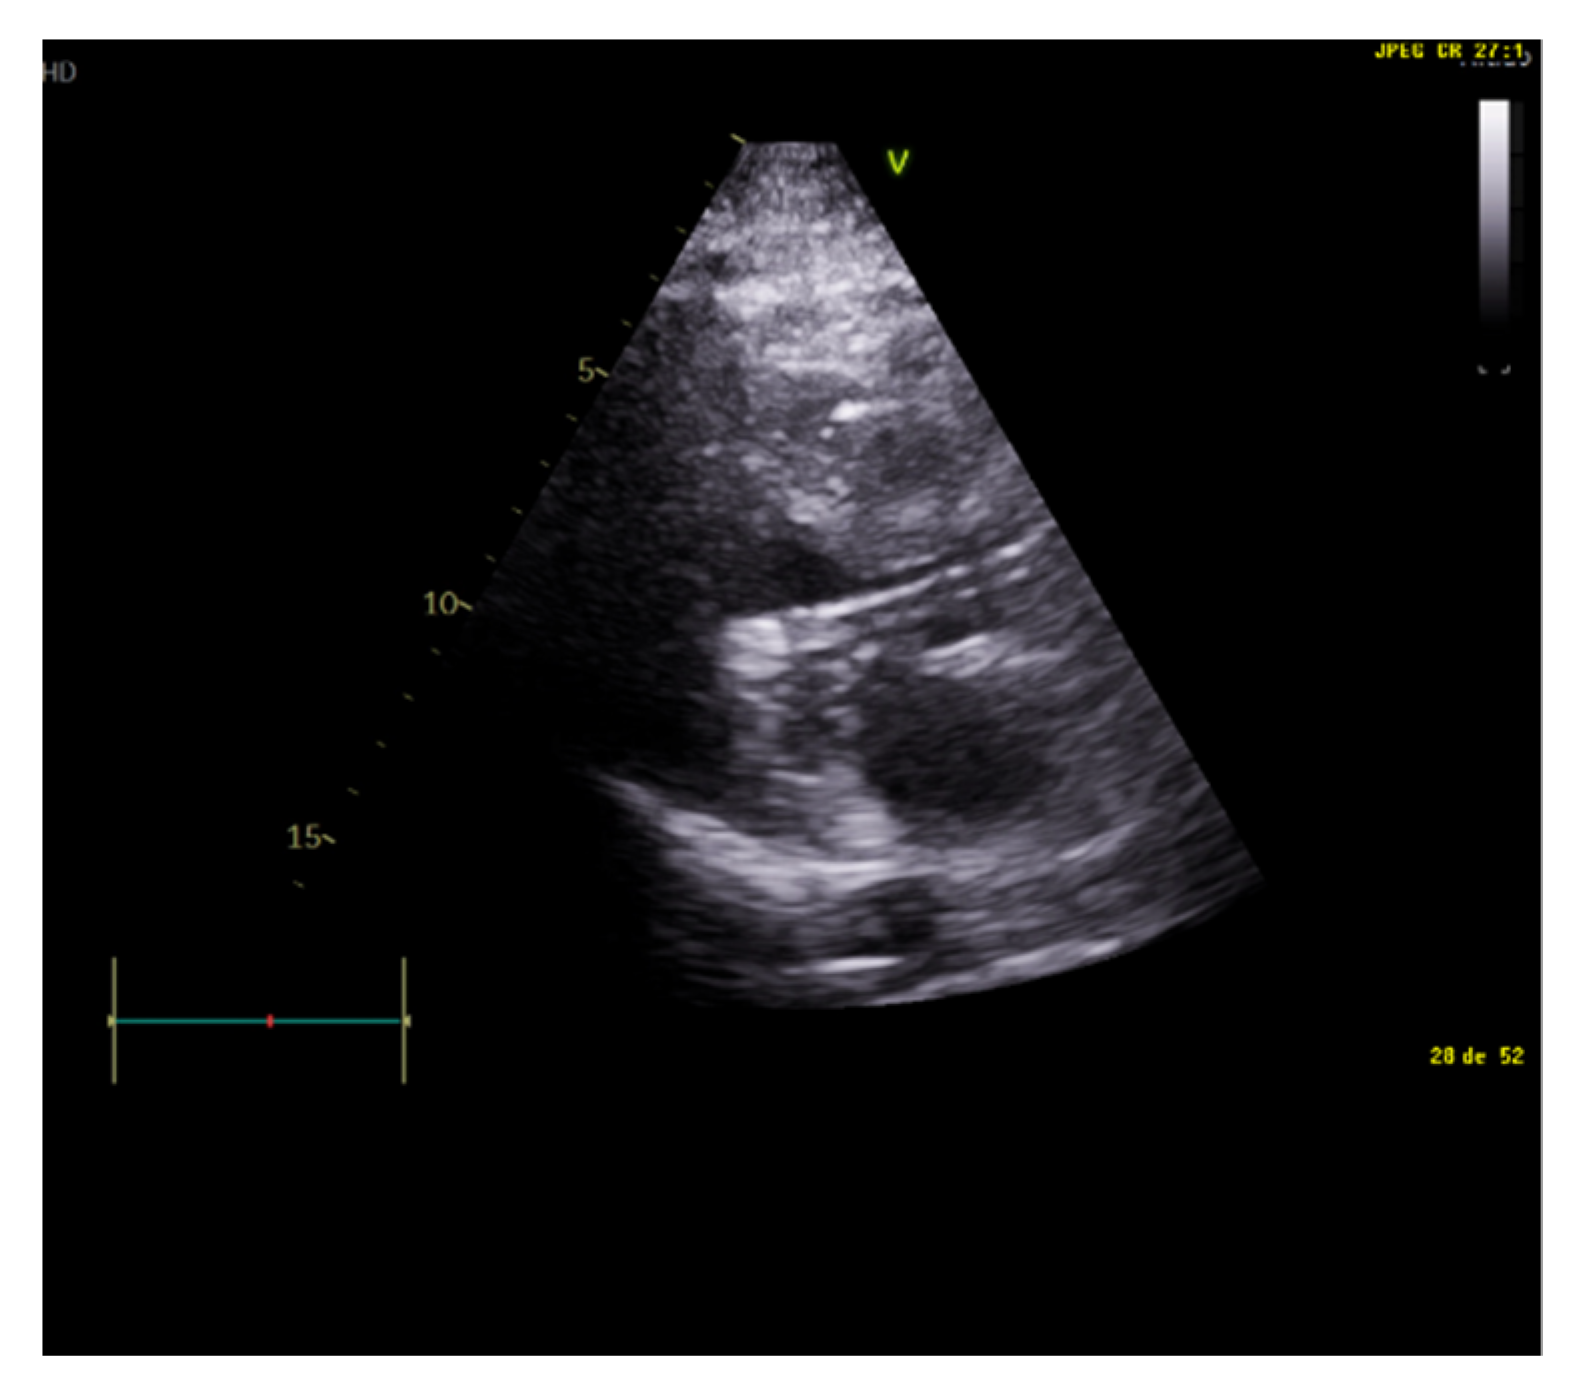

The E/A ratio is not useful in critically ill situations, as this parameter frequently suffers from a “pseudonormalization” issue [13], with a difficult quantitative interpretation. However, the presence of a “pseudonormal” or restrictive pattern is related to higher rates of weaning failure [20] (Figure 2). A reduction in the E wave deceleration time below 175 ms, in addition to other parameters which can reflect diastolic impairment, such as raised left-atrial pressure indicated by interatrial septal fixed rightward curvature and left-atrial area larger than 25 cm2, is a significant predictor of extubation failure [21]. Moreover, failure is significantly associated with a higher pulmonary capillary edge pressure and elevated pulmonary venous systolic filling [20].

Figure 2.

Restrictive diastolic filling pattern.